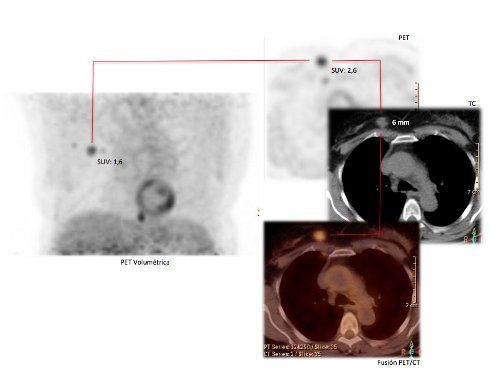

Otros estudios han demostrado que tumores pequeños (10 mm o menores) y los tumores de bajo grado son fuente de resultados falsos negativos en PET- FDG (22).

El SUV representa el índice semi-cuantitativo de captación del trazador en una determinada lesión. Es conocido y medido como la cantidad de radiotrazador presente en una lesión según la dosis administrada y se expresa en uCi/ml, normalizado al peso del paciente en Kg y la dosis administrada de FDG en mCi. El SUV se puede comparar entre controles sucesivos, objetivando apreciaciones visuales. Un SUV mayor de 2,5 orienta con mayor probabilidad a que la alteración es de origen neoplásico, en caso de duda diagnóstica.